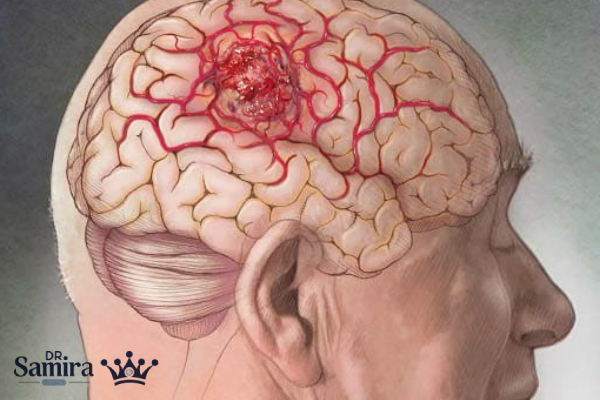

پاپیلوما کوروئید پلکسوس یکی از تومورهای نادر مغزی است که از بافت کورویید پلکسوس، یعنی ساختار مسئول تولید مایع مغزینخاعی در بطنهای مغز، منشأ میگیرد. این تومور اگرچه از نظر پاتولوژیک خوشخیم محسوب میشود، اما به دلیل محل حساس خود در سیستم عصبی مرکزی میتواند باعث اختلال در گردش مایع مغزینخاعی و افزایش فشار داخل جمجمه شود. پاپیلوما کوروئید پلکسوس بیشتر در نوزادان و کودکان خردسال دیده میشود و در صورت عدم تشخیص بهموقع، ممکن است منجر به بروز علائم عصبی جدی مانند هیدروسفالی، سردردهای شدید و تأخیر در رشد شود. آشنایی با علائم، روشهای تشخیص و راههای درمان این بیماری نقش مهمی در پیشگیری از عوارض طولانیمدت و بهبود پیشآگهی بیماران دارد.

پاپیلوما کوروئید پلکسوس زمانی ایجاد میشود که سلولهای اپیتلیالی کورویید پلکسوس دچار رشد غیرطبیعی و بیشازحد شوند. این رشد آهسته است و سلولها از نظر ساختاری شباهت زیادی به سلولهای طبیعی دارند، به همین دلیل این تومور در دسته تومورهای خوشخیم یا درجه یک (Grade I) قرار میگیرد. با این حال، یکی از مشکلات اصلی این تومور افزایش بیش از حد تولید مایع مغزینخاعی است که میتواند منجر به هیدروسفالی یا آبآوردگی مغز شود.

پاپیلوما کوروئید پلکسوس از نظر ماهیت خوشخیم است و بهندرت به سایر بخشهای مغز یا نخاع گسترش مییابد. با این حال، در صورت عدم تشخیص و درمان بهموقع، میتواند خطرناک شود. افزایش شدید فشار داخل جمجمه و هیدروسفالی درماننشده ممکن است باعث آسیب دائمی به بافت مغز، تأخیر رشد ذهنی در کودکان و حتی تهدید حیات بیمار شود. بنابراین، خوشخیم بودن این تومور به معنای بیخطر بودن آن نیست.